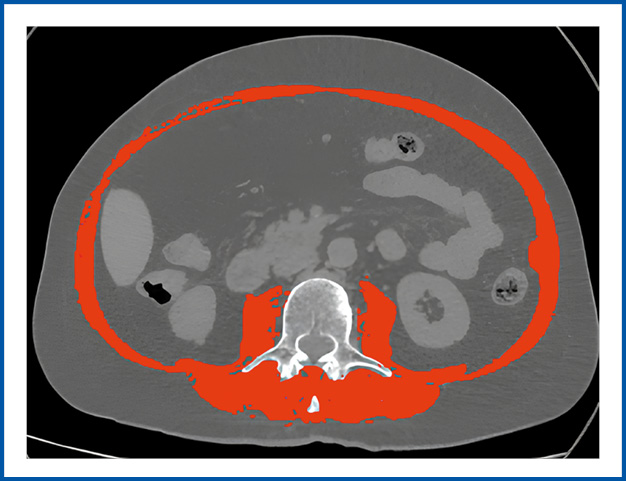

Оценка массы скелетной мускулатуры выполнялась с помощью КТ: аксиальный срез, уровень III поясничного позвонка (LIII), программа SliceOmatic, ver. 6 (TomoVision, Канада); рис. 1.

Рис. 1. Измерение площади скелетной мускулатуры с помощью КТ.

Fig. 1. Measurement of skeletal muscle area by CT scan.

При этом рассчитывался скелетно-мышечный индекс (СМИ) как отношение показателя площади скелетной мускулатуры на уровне LIII позвонка к квадрату роста пациента (м2) (см2/м2). Использовались пороговые значения, предложенные С. Prado и соавт. для когорты онкологических пациентов с ожирением (52,4 см2/м2 для мужчин и 38,5 см2/м2 женщин) [18], а также не зависящие от массы тела пациента критерии L. Martin и соавт. [19].